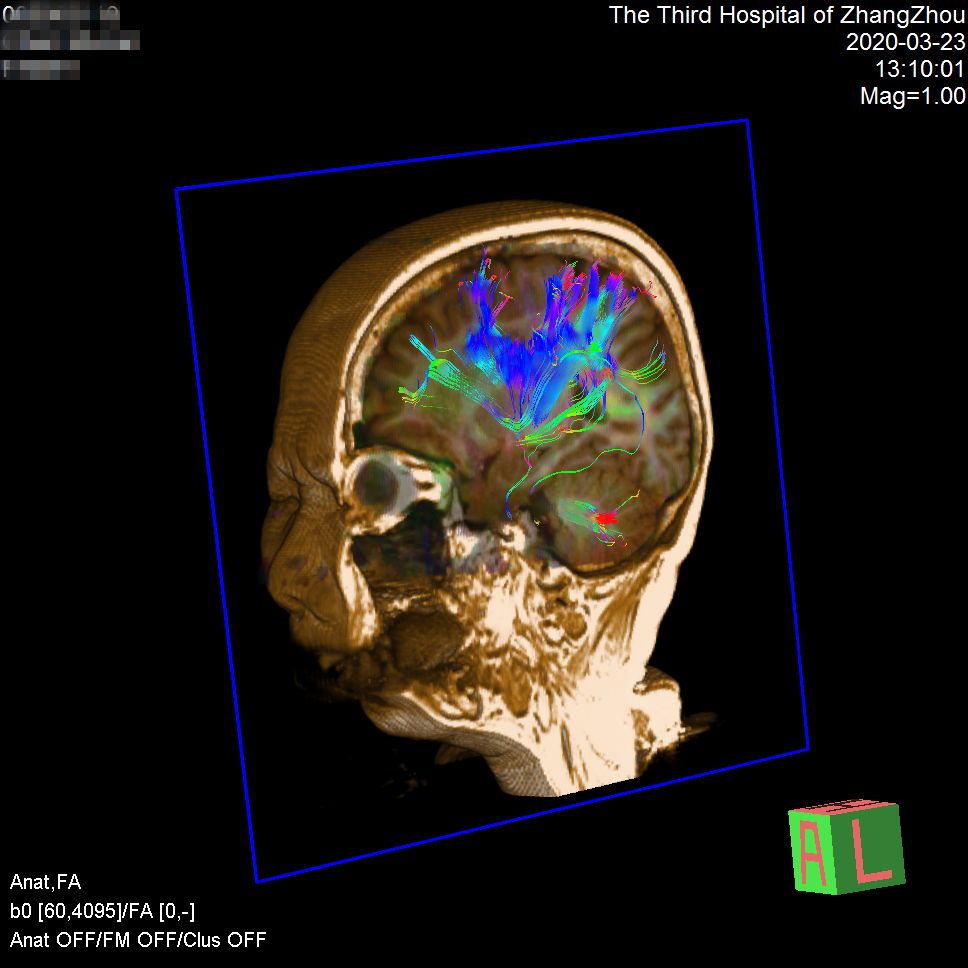

脑白质纤维束成像(DTI)